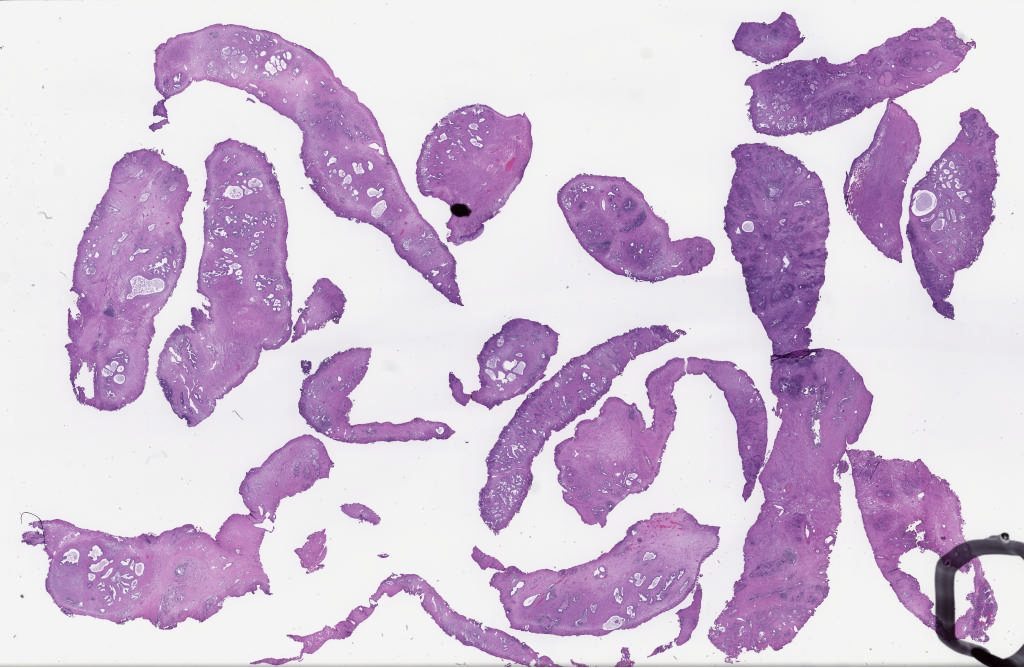

239958.svs

40X